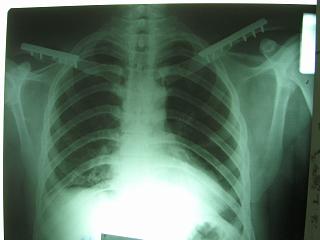

Bolnogo operirovali plastinami, snimky zdes'.

CIMG1145.JPG

Похоже, все прошло по плану. Поздравляю с успешной операцией!

Pneumatorax hirurg punctiroval i lechil dalshe, operasia zanimala 1 chas 35 minut, ni bilo problem ossobih.